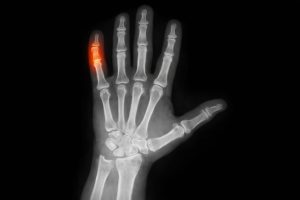

Cuando el meñique asume de manera constante la función de apoyo, se concentra carga mecánica sobre una articulación pequeña que cumple un papel relevante en la fuerza de agarre. Esta tensión sostenida puede modificar la postura de la mano y aumentar el esfuerzo sobre tendones y tejidos blandos.

Entre los síntomas descritos por especialistas se incluyen dolor localizado, rigidez, entumecimiento y dificultad para extender completamente el meñique, especialmente tras sesiones prolongadas de uso continuo del celular.